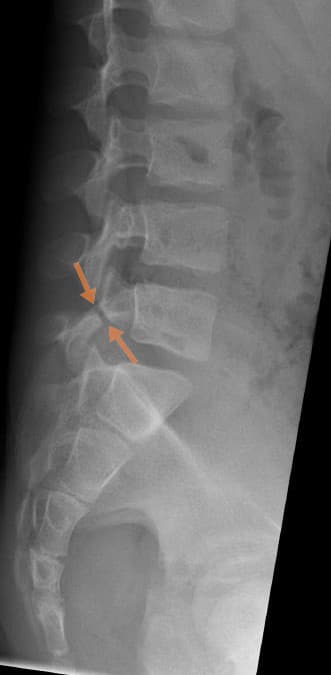

Spondylolysis is a defect or stress fracture in the pars interarticularis of the vertebral arch. The vast majority of cases occur in the lower lumbar vertebrae (L5), but spondylolysis may also occur in the cervical vertebrae. In majority of cases, spondylolysis presents asymptomatically, which can make diagnosis both difficult and incidental. When a patient does present with symptoms, there are general signs and symptoms a clinician will look for: Clinical signs: Pain on completion of the stork test (placed in hyperextension and rotation) Excessive lordotic posture Unilateral tenderness on palpation Visible on diagnostic imaging (Scottie dog fracture) Symptoms: Unilateral low back pain Pain that radiates into the buttocks or legs Onset of pain can be acute or gradual Pain that can restrict daily activities Pain that worsens after strenuous activity Pain aggravated with lumbar hyperextension Difficulty in movement in spinal cord The cause of spondylolysis remains unknown, however many factors are thought to contribute to its development. The condition is present in up to 6% of the population, the majority of which usually present asymptomatically. Research supports that there are hereditary and acquired risk factors that can make one more susceptible to the defect. The disorder is generally more prevalent in males than in females and tends to occur earlier in males due to their involvement in more strenuous activities at a younger age. In a young athlete, the spine is still growing; there are many ossification centers, leaving points of weakness in the spine. This leaves young athletes at increased risk, particularly when involved in repetitive hyperextension and rotation across the lumbar spine. Spondylolysis is a common cause of low back pain in preadolescents and adolescent athletes, as it accounts for about 50% of all low back pain. It is believed that both repetitive trauma and an inherent genetic weakness can make an individual more susceptible to spondylolysis.